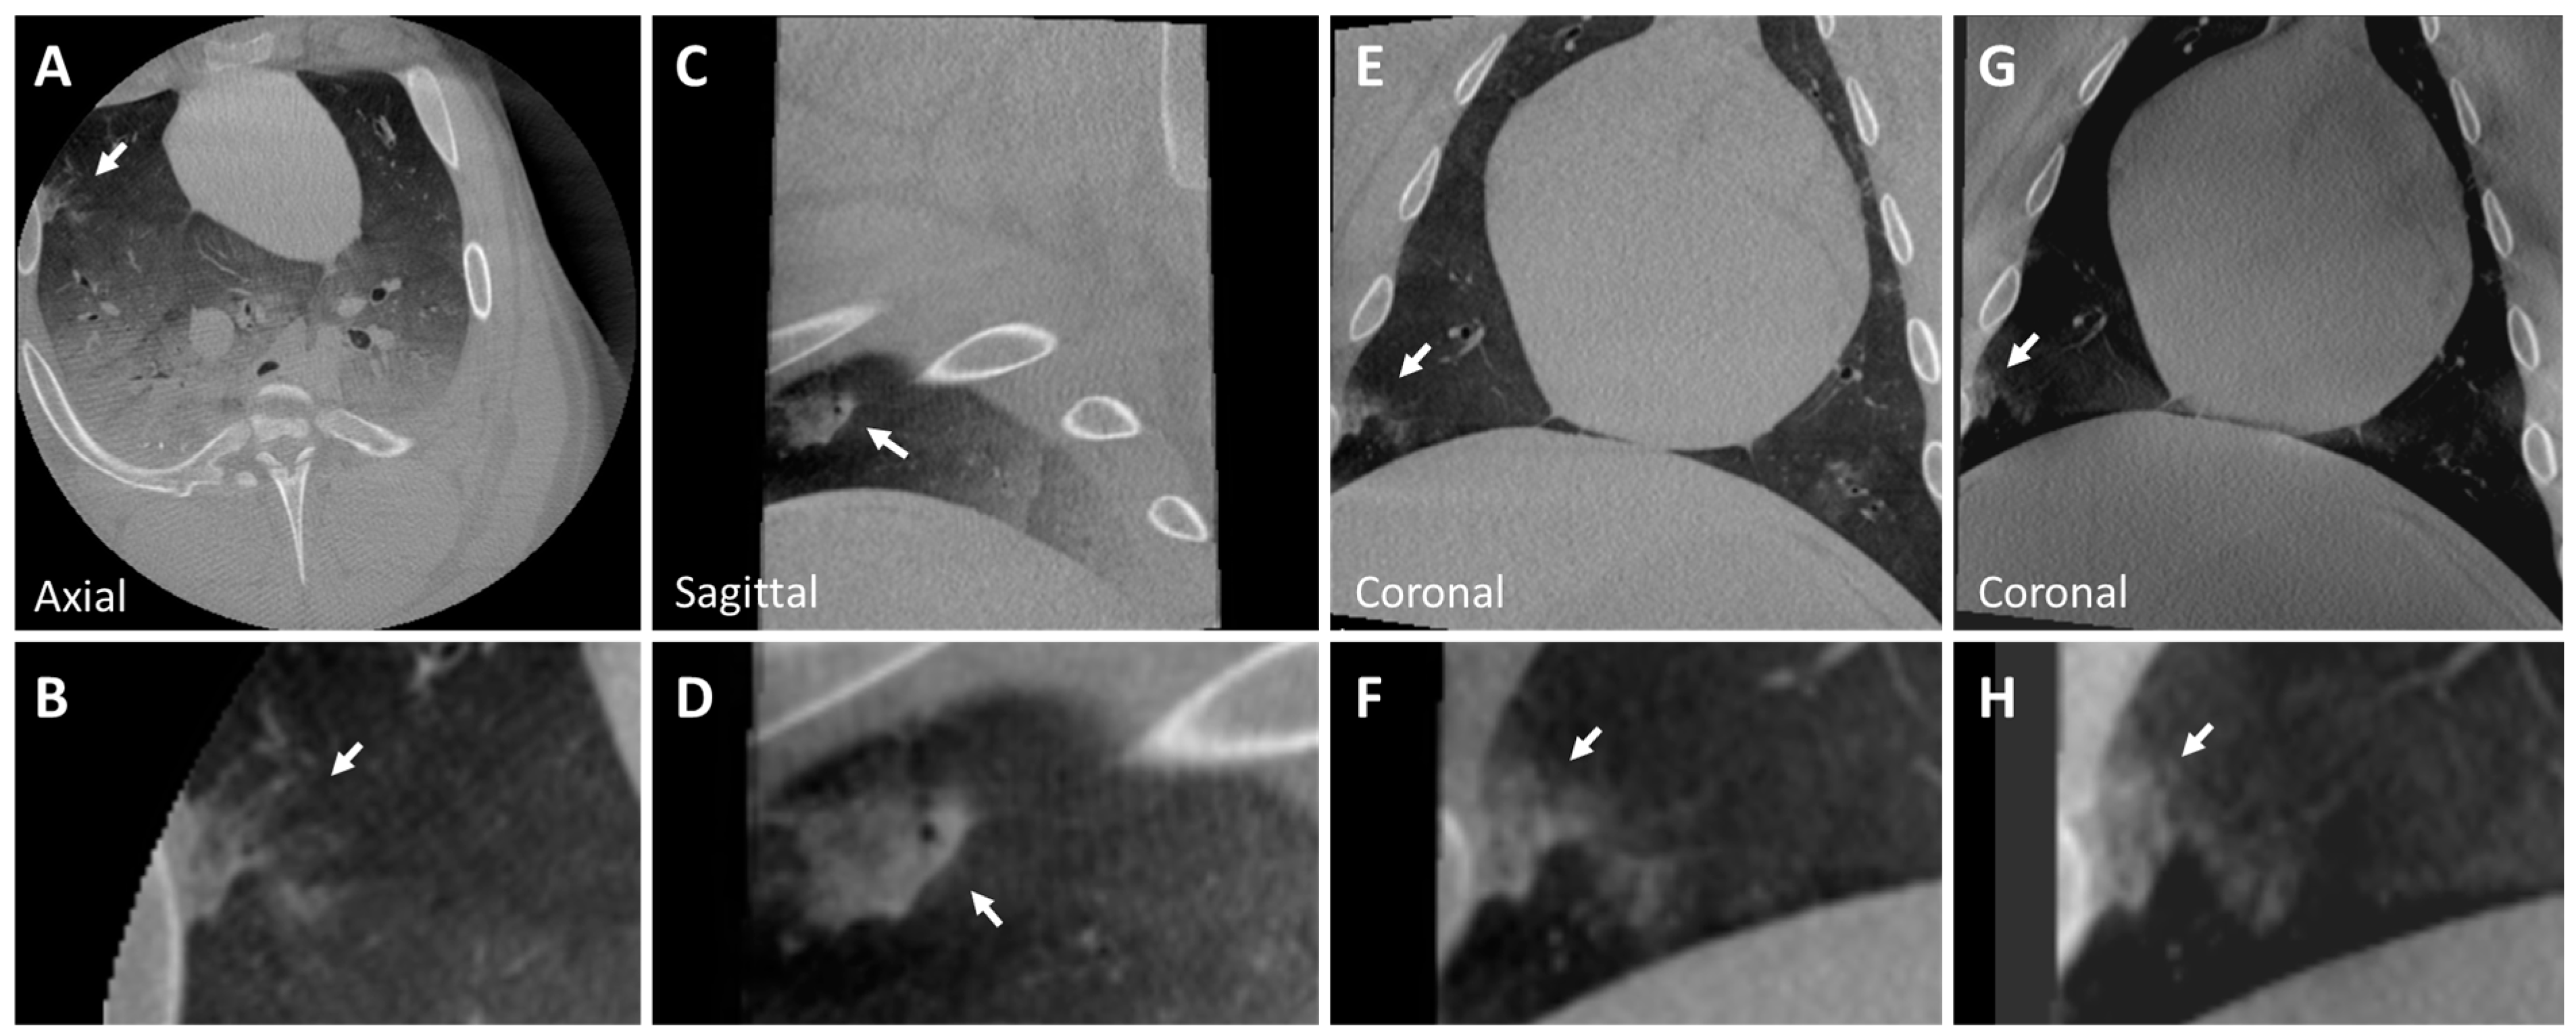

3.2. Post-Mortem Swine Lungs